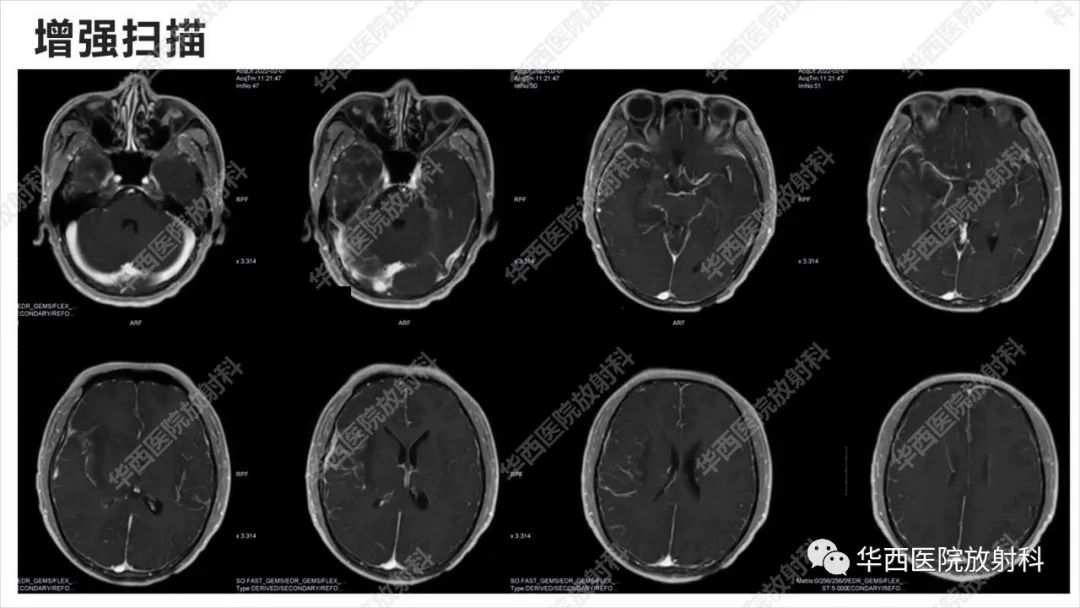

出血坏死性病毒脑膜脑炎1例CT及MR影像学表现和鉴别诊断